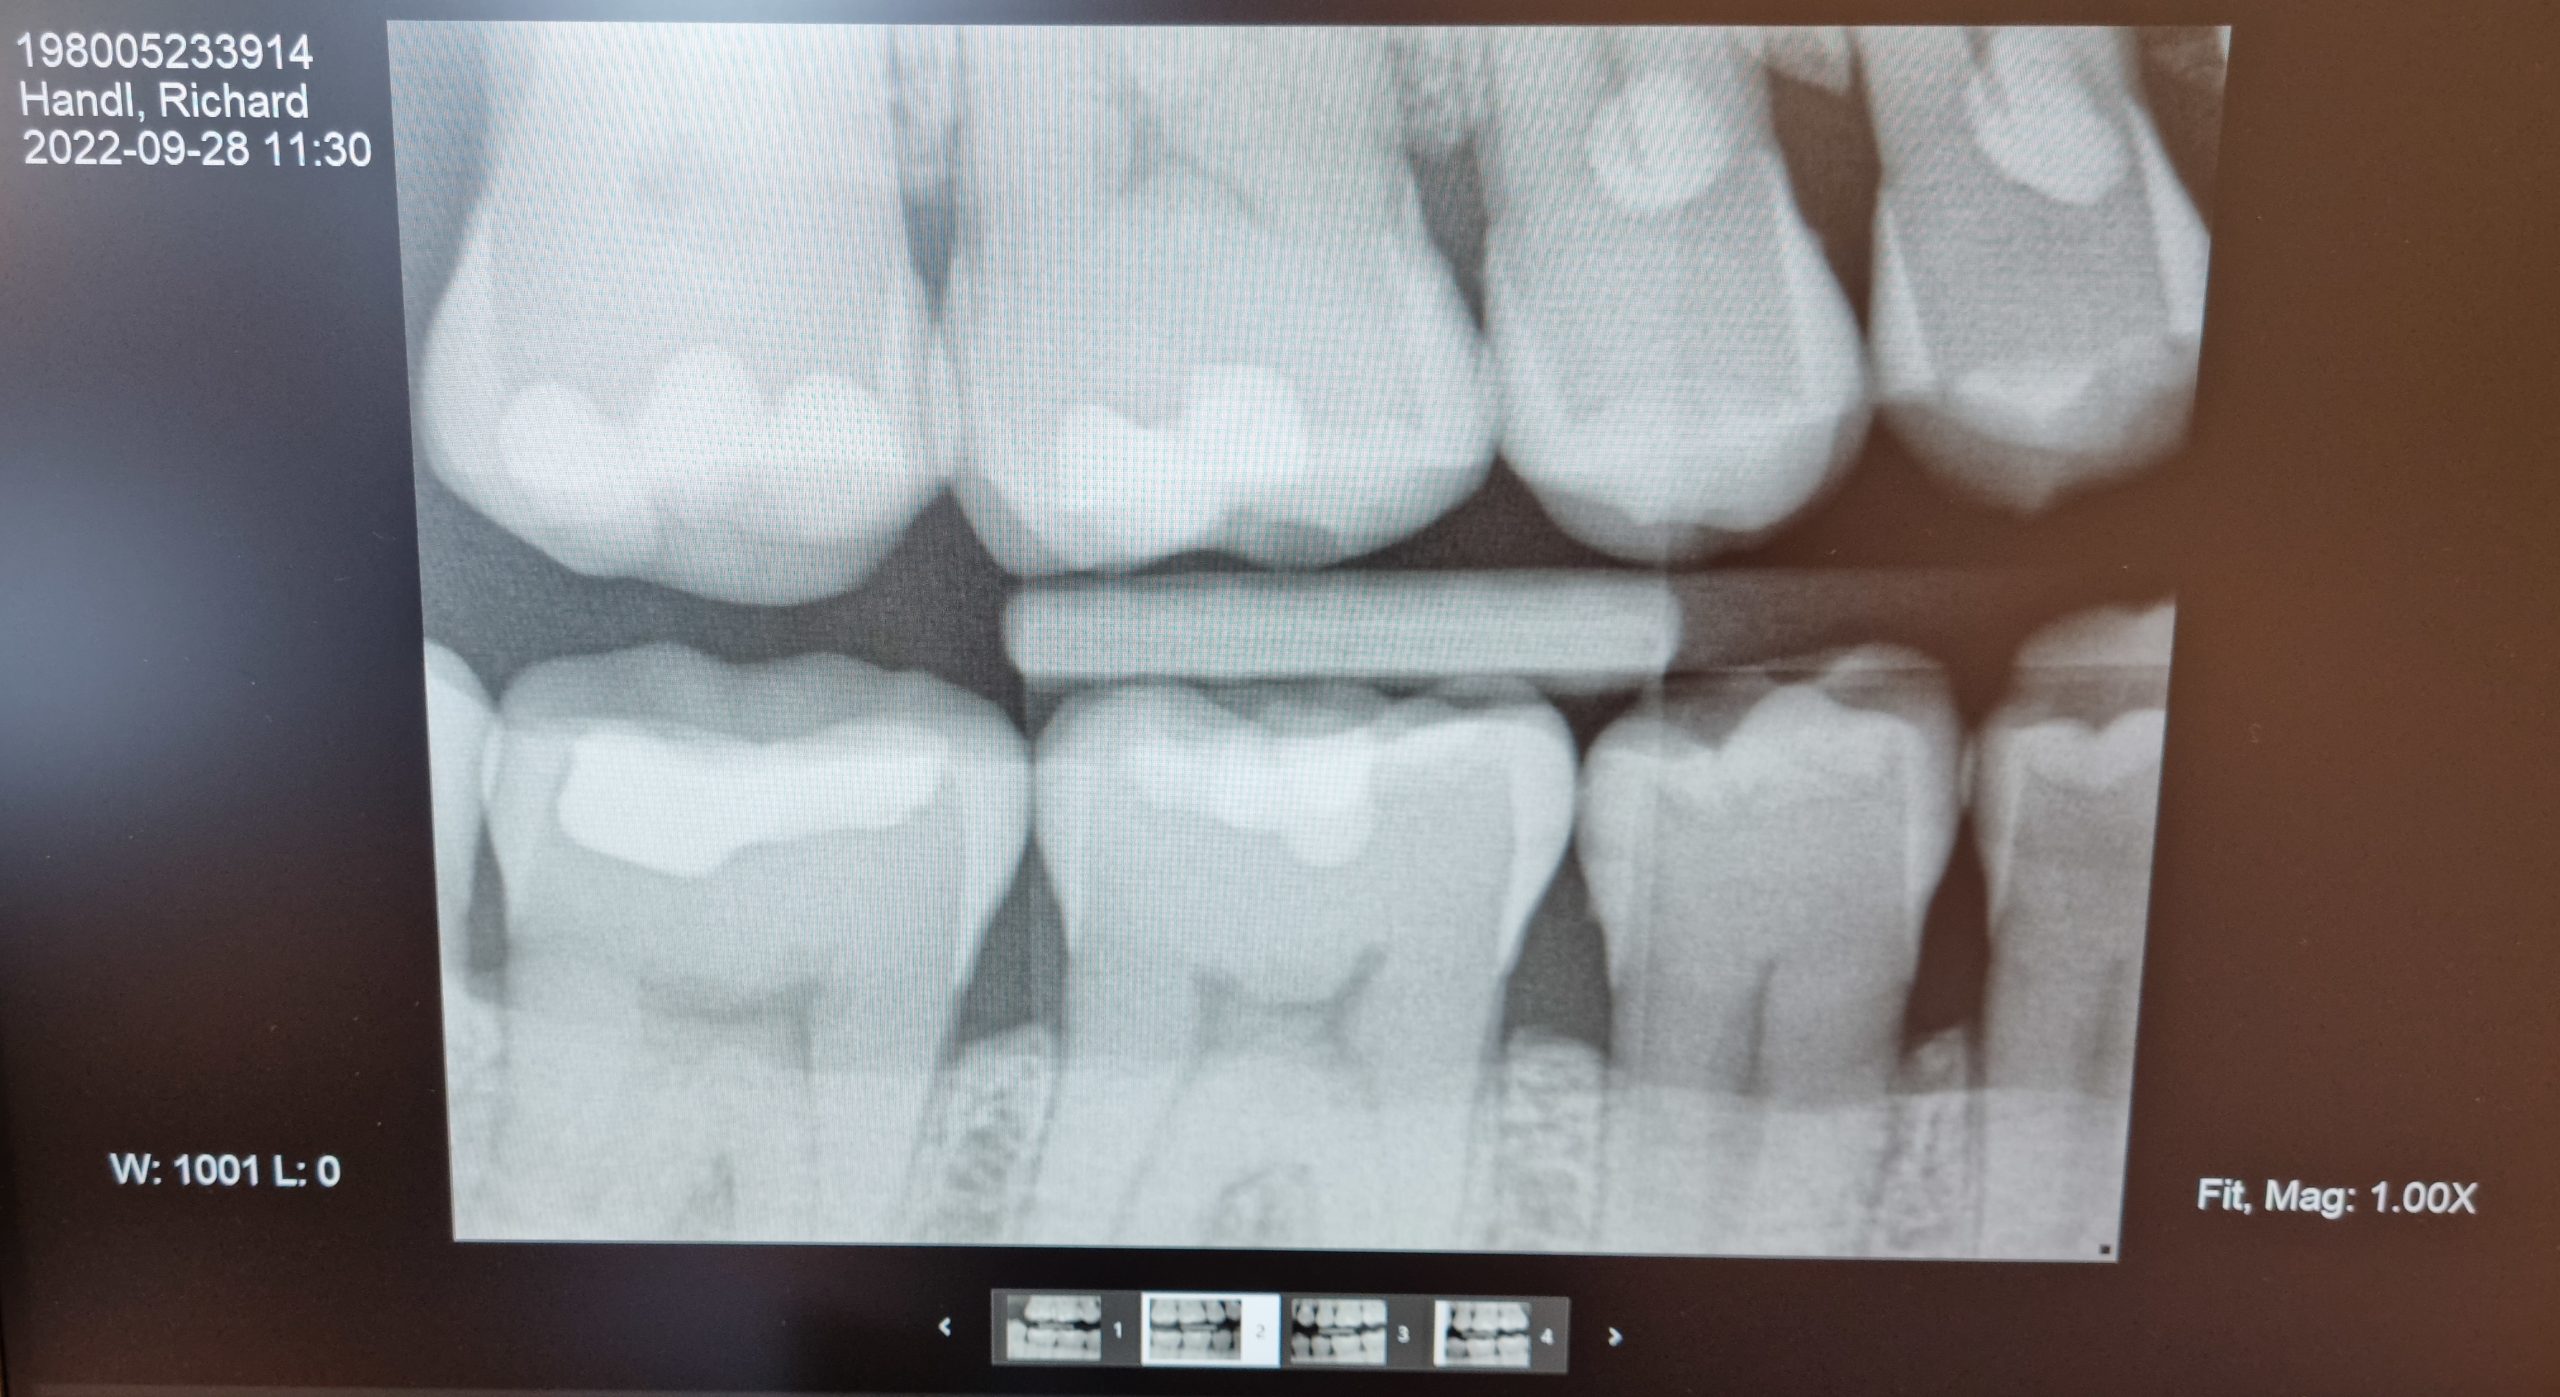

Var hos tandläkaren på morgonen. Ajajaj, mina tänder ser inte bra ut… Tandköttet är inflammerat, o när jag biter ihop, så sliter det väldigt mycket på baksidan av mina framtänder. Det blir inte bättre av att jag blir väldigt torr i munnen av en av mina mediciner (Theralen) som jag tagit i över 20 år.